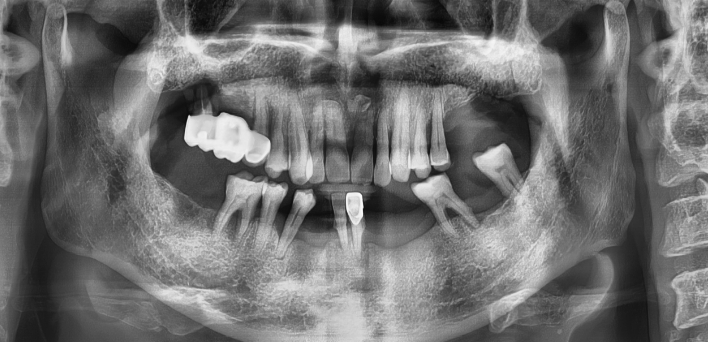

컴퓨터 분석을 활용한 임플란트

디지털 진단 후 컴퓨터 분석을 통한 모의수술 후 0.1mm 오차 없이 정확한 자리에 식립합니다.

임플란트 : 손 ** 님 (50대)

치아가 있다는게, 아직도 정말 꿈만 같아요.

Before Before

2020.02.30

After After

※ 더서울치과의원은 의료법을 준수하며 위 케이스는 실제 환자의 동의를 얻은 사례로 치료 전, 후가 동일한 환경에서 촬영되었습니다.

환자 케이스에 따라 부작용이 발생할 수 있습니다. 이 부분은 의료진의 충분한 상담과 체크를 통해 예방하고 줄일 수 있습니다.

[임플란트 부작용] 수술 후 관리가 소홀할 경우 출혈, 주위염 등의 부작용이 발생할 수 있어 구강 위생을 철저히 유지하고, 정기적인 검진을 통해 상태를 점검하는 것이 중요합니다.

환자 특징

환자 특징01무치악 상태

환자 특징02수년간 무치악으로 지내심

임플란트가 불가능할것이라

생각하고 내원

위, 아래 6개씩 식립

디지털 풀아치 임플란트

더서울치과의원은 다수의 임플란트 수술 경험을 토대로 정확한 디지털 기반 진단,

환자에게 가장 적합한 수술 방법으로 내 치아처럼 오래 사용하는 임플란트를 식립합니다.

임플란트 Before & After